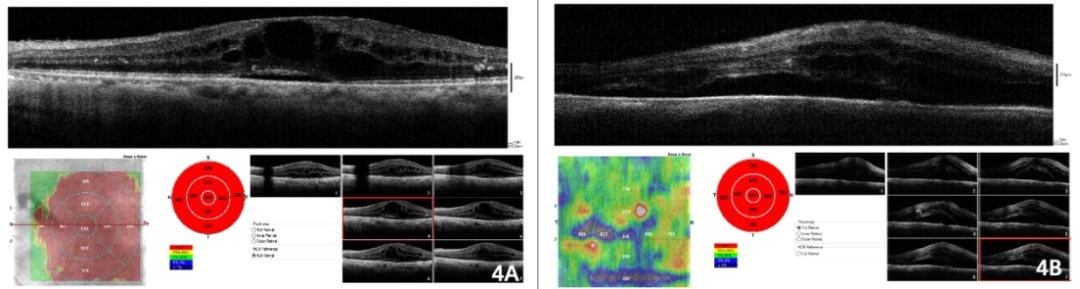

图4. 术前窥不清眼底的2位糖尿病合并年龄相关性白内障患者,术中采用iVue OCT观察眼底所见。4A示黄斑区囊样水肿;4B示中心受累的黄斑水肿